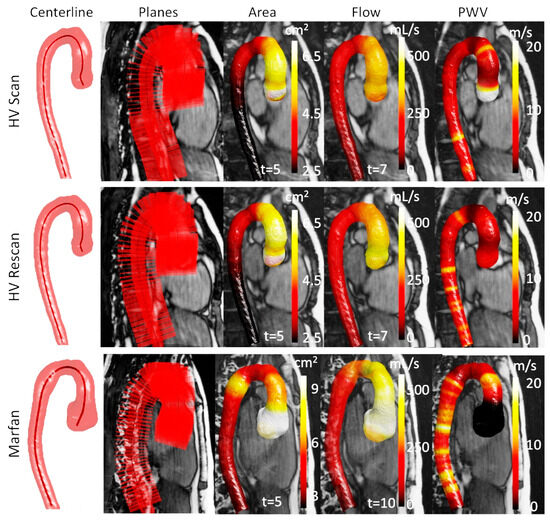

1. Introduction

2. Materials and Methods

2.4. Area and Flow Measurements

2.5. Local PWV Calculation